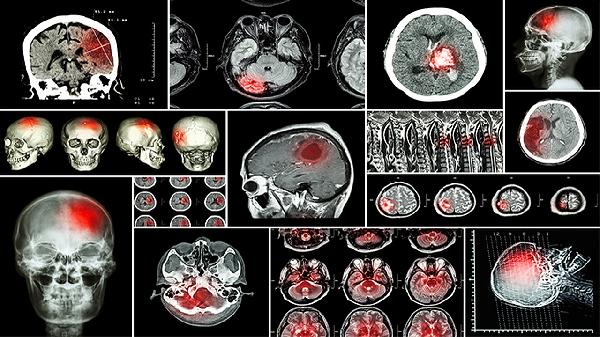

闭合性颅脑损伤后遗症主要有头痛头晕、认知功能障碍、情绪障碍、运动功能障碍、癫痫发作等。闭合性颅脑损伤是指头部受到外力作用,但颅骨保持完整,脑组织受到损伤的一种情况。